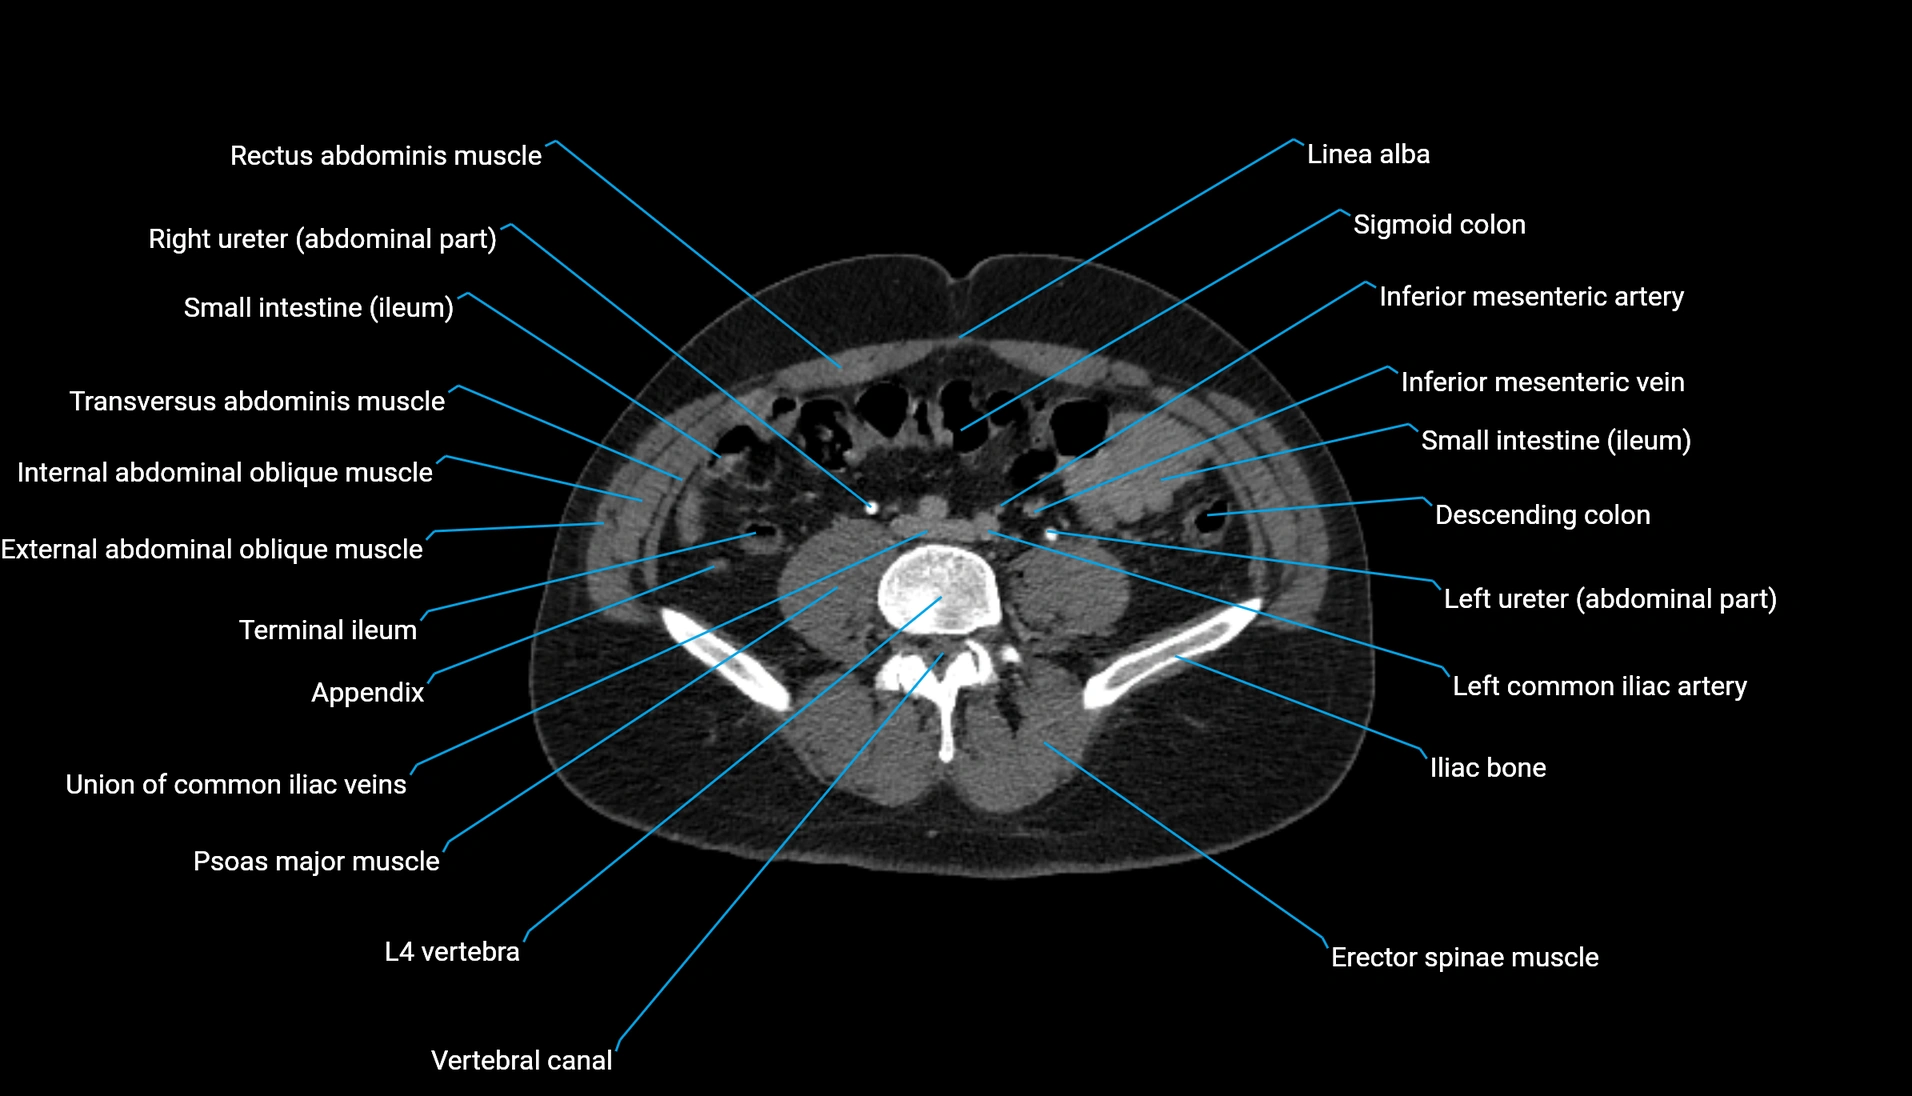

CT VRT 3D image

CT image